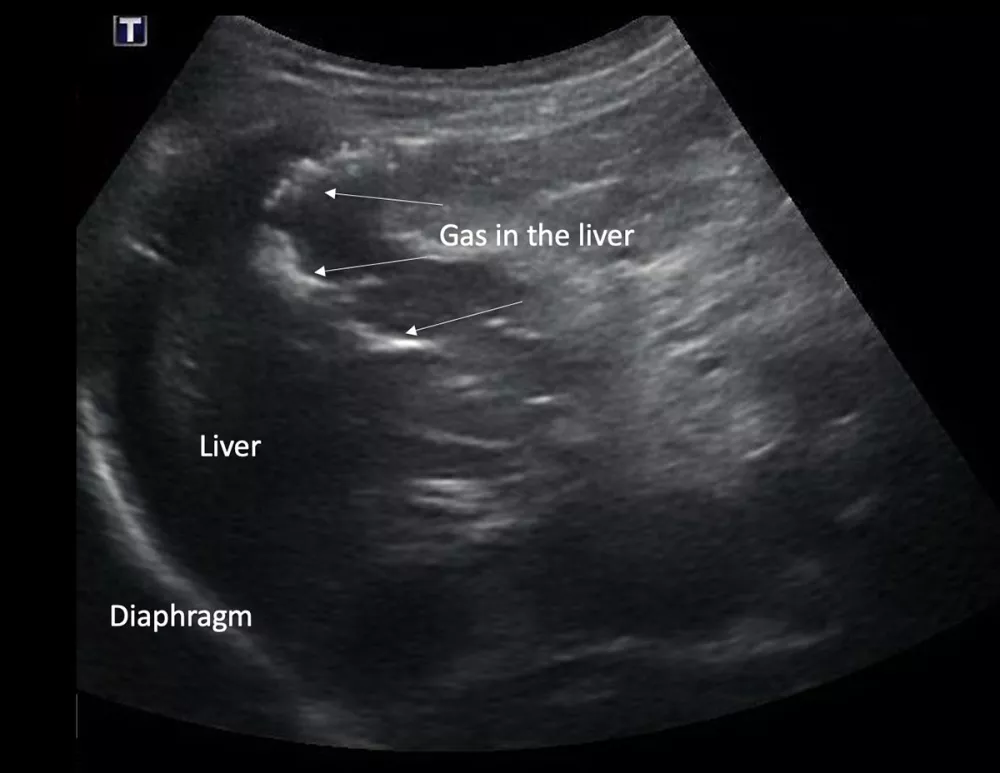

Imaging of a 1-year-old neutered male standard poodle presented with anorexia, lethargy, vomiting, hypoalbuminemia, hypoproteinemia, and cranial abdominal organomegaly. Transverse (A) and sagittal (B) ultrasound of the liver and gallbladder (GB). The liver is enlarged (with increased distance off the stomach from the diaphragm, rounded borders, and extension ventral to the stomach), diffusely hyperechoic, and homogenous. The gallbladder is moderately distended with a normal wall and content. Radiographs demonstrate hepatomegaly and splenomegaly (C). Abdominal ultrasound images revealed splenic enlargement with a mildly mottled architecture and a solitary hypoechoic nodule (D; arrowheads). The pancreas is enlarged and lobulated with multiple hypoechoic tracts and a peripheral capsule (E; between electronic cursors [X’s]). The jejunal lymph nodes are severely enlarged (F; between electronic cursors [X’s]), more than expected for a young dog. The combination of severe hepatosplenomegaly and lymphadenomegaly make systemic disease (eg, infectious, neoplastic) most likely. The appearance of the pancreas is due to pancreatic edema secondary to hypoproteinemia. Acute liver injury was diagnosed, and lymphoma was diagnosed based on hepatic and splenic cytology.